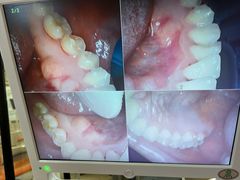

• 藁城德伦口腔医院

• -藁城德伦口腔医院

点小评8248430575 | 22-05-11

点小评6093712728 | 22-05-08